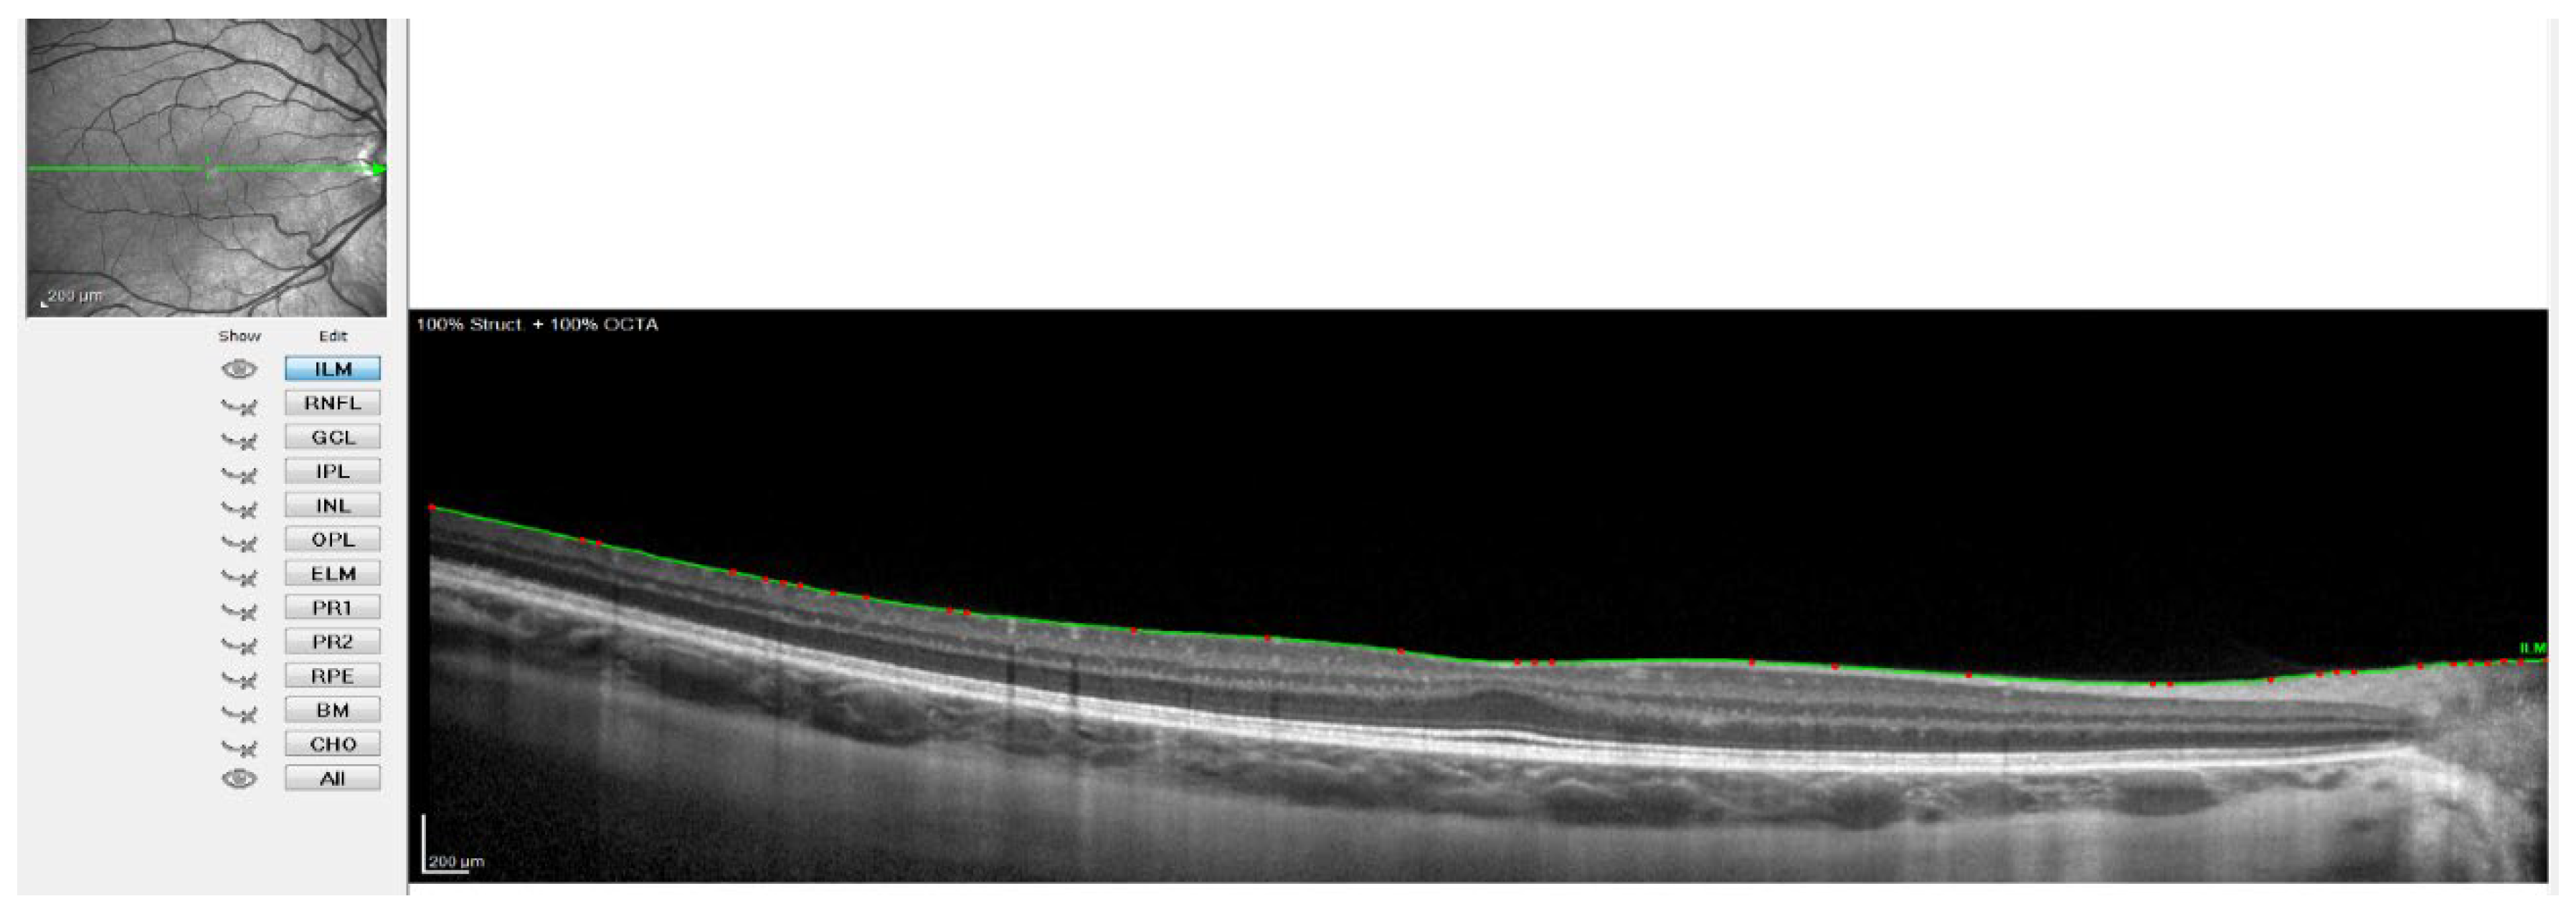

Figure 2.

OCT image with the line of the internal limiting membrane marked in green, point by point.

Figure 2 shows when the internal limiting membrane was used to manually mark the division line between the choroid and sclera, moving that line point by point. Figure 3 shows the result of the movement of the line to define the sclero-choroidal interface.